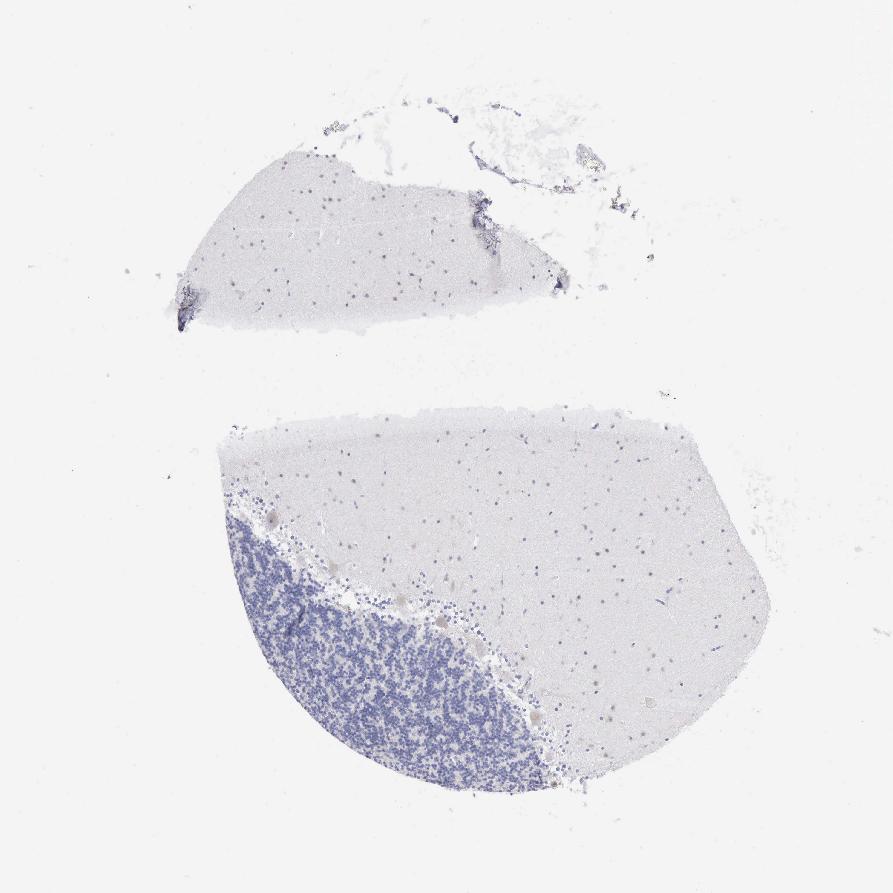

CEREBELLUM - Antibody stainingi

Antibody staining in the annotated cell types in the current human tissue is reported as not detected, low, medium, or high, based on conventional immunohistochemistry profiling in selected tissues. This score is based on the combination of the staining intensity and fraction of stained cells.

Each image is clickable and will lead to virtual microscopy that enables deeper exploration of all samples and also displays staining intensity scores, fraction scores and subcellular localization as well as patient and tissue information for each sample.

Antibody HPA000948

Purkinje cells Low

Cells in granular layer Not detected

Cells in molecular layer Not detected